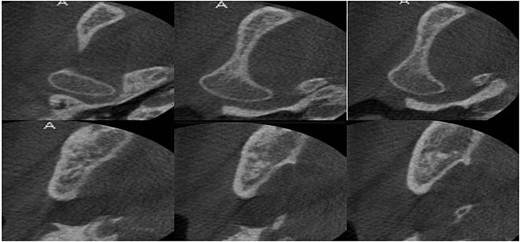

Computed tomography after 12 months showed a bone regeneration in the lesion’s area and the cystic lesion has become completely surrounded by thick bony plates.

After 12 months, the second stage was performed to remove the lesion (Fig. 6). Under general anesthesia, enucleation with peripheral ostectomy was performed. A flap was developed to expose the anterior border and most of the lateral surface of ramus. The lining of the lesion was detached from the bony walls. A surgical bur was used to remove bone adjacent to the cystic lining. After enucleation, the cavity was filled with gelfoam and the incisions were closed with 4–0 Prolene suture. The patient returned regularly for follow-up after every 3 months (Fig. 7). The total follow-up period so far was 36 months. Cone beam computed tomography (CBCT) scan after 24 and 36 months showed no evidence of lesion recurrence and great bone formation (Fig. 8).

Cone beam computed tomography after 30 months showed full healing without any recurrence.